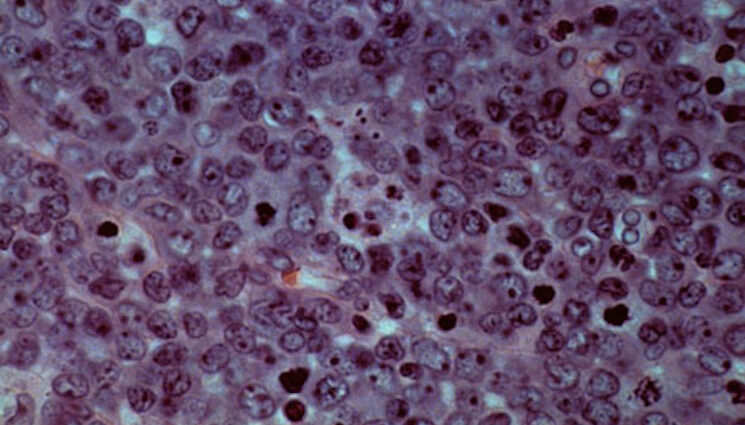

Allogene Therapeutics said Monday that its off-the-shelf CAR-T treatment eliminated residual cancer cells in patients with B-cell lymphoma three times better than standard care — achieving the interim goal of an ongoing Phase 3 clinical trial.

In the interim analysis, 58% of patients treated with the Allogene CAR-T, called cema-cel, achieved minimal residual disease, or MRD, negativity compared to 16% of patients who were observed but not treated.